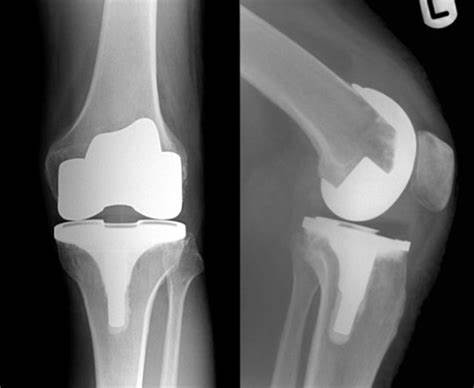

大部分下蹲困难的患者,往往软骨的退变不是单纯的。与之相一致,我们会发现这些患者膝关节的内外侧软骨也可能已经受到不同程度的影响,这个时候最佳的治疗方案是膝关节表面置换手术:就像牙齿坏了进行镶补一个道理,把受损的关节软骨面磨去,为关节做一个全面的清创和护理之后,镶上人工关节配件。近年来推行的快速康复理念(涉及手术技术、血液管理、疼痛管理和术后复健计划等的综合概念)更是让膝关节表面置换手术日趋完美。

TKA手术

如果将人的膝关节比喻为一辆汽车的轮胎,软骨的磨损往往等于是车轮外胎破损,但是发动机及其他动力系统是好的,只需要进行适当的维修,将外胎(即软骨面)修补好便可以恢复正常运转。因此,人工关节置换后实现的快速康复也是理所应当的,只要做到术中规范、术后专业护理,快速康复的质量是能够得到保证的。

双膝骨关节炎行双侧膝关节表面置换术